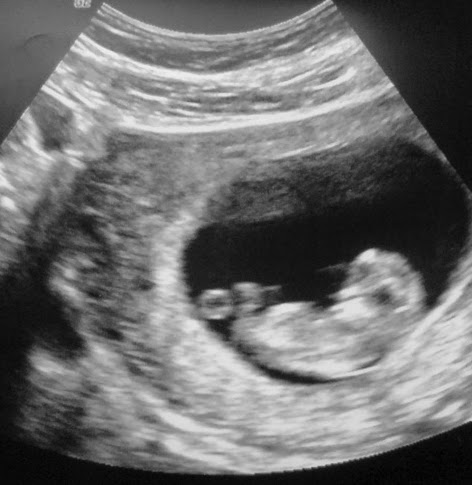

At that point, her unborn baby was barely over an inch long but already growing tiny fingernails. Doctors told Ashley that her baby would likely not survive the chemo treatments. And here is what Ashley says about that:

Juxtapose that with the reality that many young women today have abortions for many far less deadly reasons. In fact, of the 1.24 million abortions in America each year, the majority take place between 8-10 weeks of pregnancy.

10-week gestation photo: andrew k via photopin cc